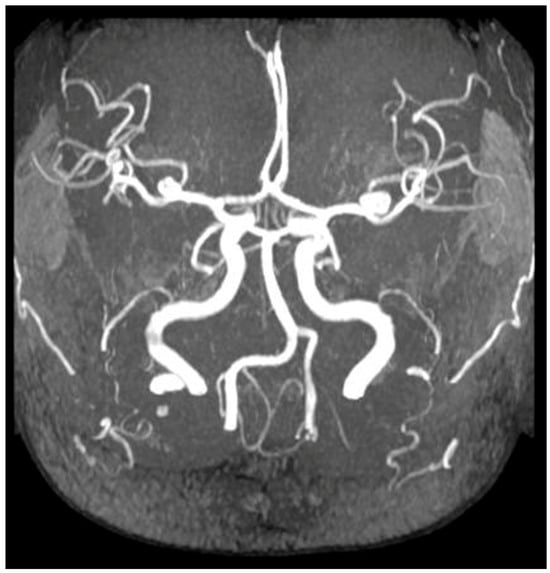

- Capelli, I.; Zoli, M.; Righini, M.; Faccioli, L.; Aiello, V.; Spinardi, L.; Gori, D.; Friso, F.; Rustici, A.; Bortolotti, C.; et al. MR Brain Screening in ADPKD Patients: To Screen or not to Screen? Clin. Neuroradiol. 2022, 32, 69–78. [Google Scholar] [CrossRef]

- Haemmerli, J.; Morel, S.; Georges, M.; Haidar, F.; Chebib, F.T.; Morita, A.; Nozaki, K.; Tominaga, T.; Bervitskiy, A.V.; Rzaev, J.; et al. Characteristics and Distribution of Intracranial Aneurysms in Patients with Autosomal Dominant Polycystic Kidney Disease Compared with the General Population: A Meta-Analysis. Kidney360 2023, 4, e466–e475. [Google Scholar] [CrossRef] [PubMed]

- Xu, H.W.; Yu, S.Q.; Mei, C.L.; Li, M.H. Screening for intracranial aneurysm in 355 patients with autosomal-dominant polycystic kidney disease. Stroke 2011, 42, 204–206. [Google Scholar] [CrossRef] [PubMed]

- Niemczyk, M.; Gradzik, M.; Niemczyk, S.; Bujko, M.; Gołębiowski, M.; Pączek, L. Intracranial aneurysms in autosomal dominant polycystic kidney disease. AJNR Am. J. Neuroradiol. 2013, 34, 1556–1559. [Google Scholar] [CrossRef]